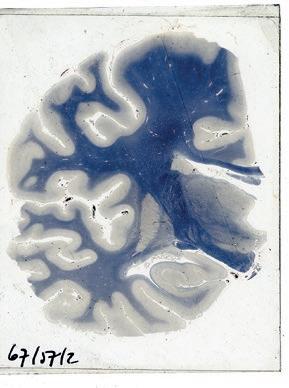

Study of the brain by Professor André Dewulf, twentieth century,

Professor André Dewulf’s Brain-Cutting Machine, twentieth century, photograph. Dr. Guislain Museum, Ghent

The first X-rays of Wilhelm Röntgen (1845–1923) in the twentieth century didn’t just affect psychiatry, they led to the creation of other medical disciplines. In a strange way, Röntgen, Freud, Turing and Einstein entered the new century hand in hand, ensuring the genesis of more refined and more specific methods of examination. With the arrival of the computer in the second half of the twentieth century, the evolution went even faster. In the middle of this technological hurricane, Professor André Dewulf (1903–2000) was working in an attic on his own polytoom for neuroanatomy research at the Sint-Kamillus University Psychiatric Centre in Bierbeek. The device, made of rusty metal and parts that were actually intended for the building industry, allowed him to take fine slices of brain tissue for study under the microscope. Dewulf conducted groundbreaking research into the structure of the hypothalamus with it. Thanks to the insights of contemporary physics, we are now further advanced today in studying the brain. Neurologists can dig deeper and use diverse techniques to undertake more specific research.

Illustrations from: Gerbrandus Jelgersma, Atlas anatomicum cerebri humani. 168 doorsneden van menschelijke hersenen, 108 lichtdrukplaten naar photographische opnamen van praeparaten, 1931, Amsterdam. Dr. Guislain Museum, Ghent

Gerbrandus Jelgersma (1859–1942) is known for his research into neuroanatomy and the famous brain atlas he worked on for 25 years. The anatomy of the brain played an important part in his thinking about conditions such as neurasthenia, hysteria, chorea and epilepsy. He believed at the beginning of his career that every sickness could be traced to a defect in the body, but he later became interested in the ‘unconscious mental life’ and in Freud’s insights into the subconscious. Jelgersma supplemented his neurological and anatomical knowledge with opinions from fields where psychological approaches were applied.